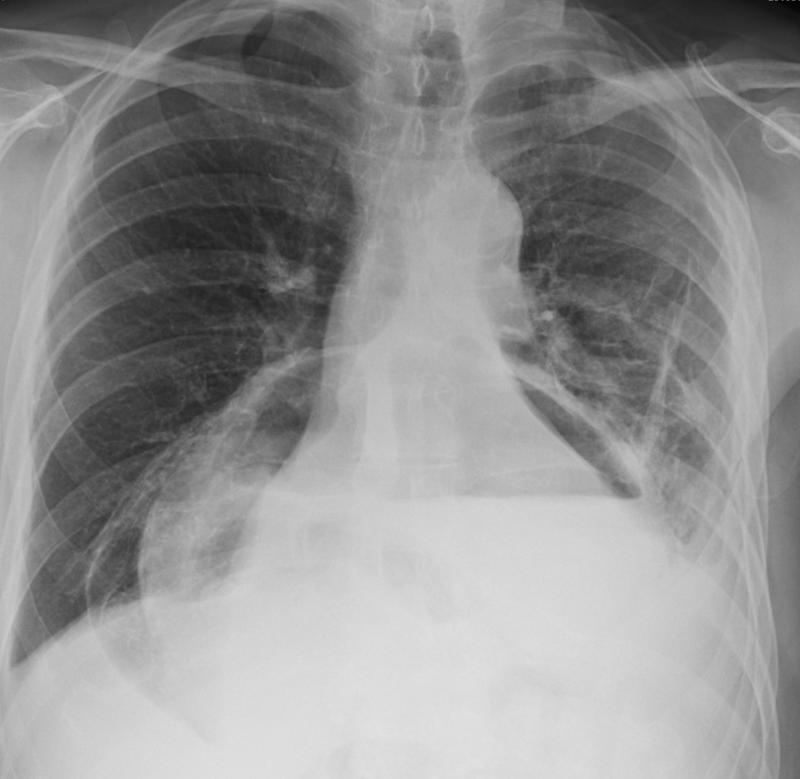

Mediastinum

Hiatus Hernia

Hiatus hernia containing stomach and transv colon

Hiatus hernia containing

stomach and transv colon